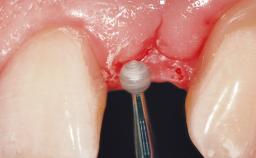

Immediate Flapless Placement of an Implant in a Maxillary Left Central Incisor Site

A 29-year-old female patient presented for treatment to replace the upper left central incisor tooth with an implant- supported restoration. The tooth had been intermittently symptomatic for the previous 12 months. The tooth had originally suffered trauma about 15 years previously. Several endodontic treatments had been performed, including an apicectomy procedure to retain the tooth. The patient was healthy and a non-smoker. She had reasonable expectations in regard to esthetic outcomes and the risk of marginal tissue recession following treatment. At medium smile, the gingival margins of the upper teeth were visible, with a display of 3 to 4 mm of the gingival margins. Gingival recession of tooth 21 and a discrepancy in the gingival levels between teeth 11 and 21 was observable during normal speech and smile.

Soft Tissue Anatomy Intact Defective

Soft Tissue Contour and Volume Slightly compromised